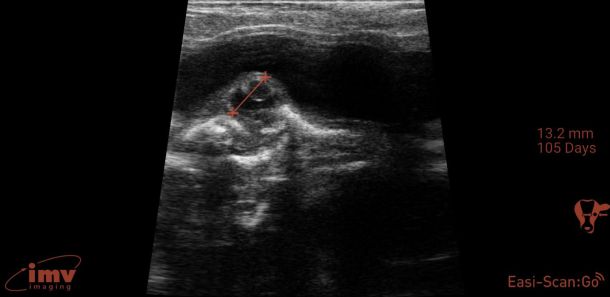

Ageing and foetal assessment

Detailed ultrasonography can detect pregnancy from 22-24 days post-insemination but due to higher rates of loss and inconsistency in quickly detecting the foetus, it is advisable that ultrasonographic pregnancy diagnosis at 28-30 days post-insemination is performed as it becomes very reliable (see Photo 2)2. At this point, the embryo becomes visible as a small, echogenic (white) structure suspended within the black (anechoic) uterine fluid2. Beyond this point, ageing is performed by either measuring or ‘eyeballing’ foetal crown-rump length, head or trunk diameter, head length or eyeball diameter (for references lengths see Table 1)6,7. Modern ultrasound machines will automatically give an estimated days in-calf, if the image is frozen and a distance is measured, but the author finds that the grid function (where a box represents 10mm) is a more useful way to eyeball these measurements without having to freeze the image. Thus thinking in boxes allows the user to reliably age using the crown rump length up to day 60 and then using head diameter and/or eyeball from days 60-150 days (see Photo 3). Measuring the placentomes is not a very reliable method to accurately age owing to the fact that placentome size will vary depending on where in the horn it is located, with smaller placentome being at the edge of the horns2.

Foetal heartbeat can be used to assess foetal viability and it is detectable from early pregnancy examination (i.e., 28 days onwards)2. Not many practitioners will measure the rate but will, rather, check for presence/absence to assess foetal viability. If heart rate is measured, it is typically 160 to 200 beats per minute (bpm) in early gestation and this can reduce to closer to 100-120bpm in later gestation. Other things that can be assessed for viability are: foetal movement, the appearance of allantoic and amniotic fluid and foetal morphology. Lack of foetal movement, abnormal cloudy fluid, and abnormal foetal appearance for the stage of gestation, are signs the pregnancy is being resorbed or lost or deformed2.